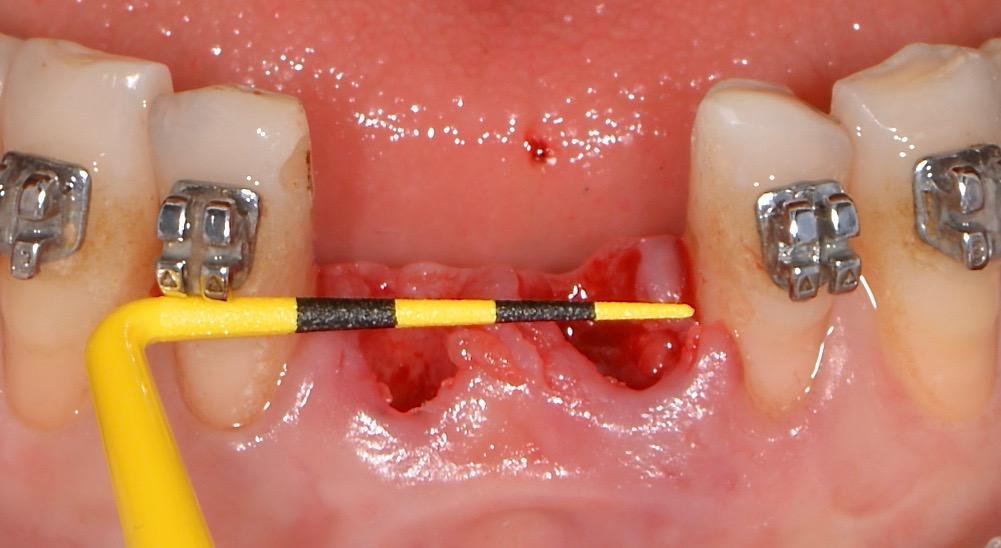

Classe 3: nesta situação, há uma perda da parede óssea vestibular que compromete a arquitetura do alvéolo. O objetivo da técnica não é só manter o alvéolo após a exodontia e sim reconstruir o formato deste. A técnica indicada é a seguinte:

1º – Após a exodontia e as manobras de avaliação do alvéolo com auxílio de um tunelizador é realizado um descolamento subperiostal 3mm para lateral e apical do defeito ósseo sem que se levante retalho;